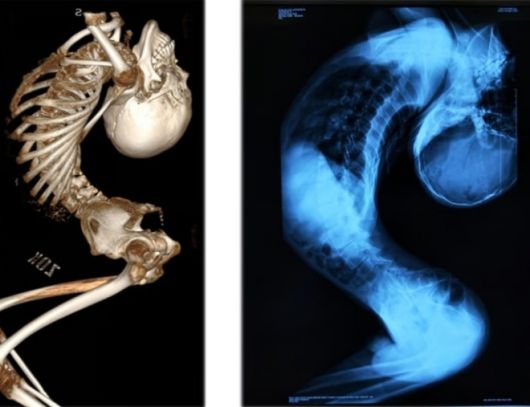

중국 산둥성 출신인 장씨는 척추 관절과 인대에 심각한 염증을 일으키는 희귀 질환인 ‘강직성 척추염’을 앓아 목과 척추가 뒤로 심하게 굽은 채 살아왔다.

이 희귀한 질환으로 인해 그의 몸은 ‘Z자’ 형태로 접혀 머리와 엉덩이 간격은 손바닥 한 뼘에 불과했고, 접힌 키는 80cm에 불과했다.

이후 지난해 8월 그는 청두의 척추 교정 권위자인 량이젠 교수에게 경추·흉추·요추 절골술과 고관절 교정 등 총 4차례의 대수술을 받았다.

지난 6월 받은 마지막 수술은 12시간 넘게 이어졌으며, 그의 척추는 약 170도 교정됐다.

그 결과 그는 처음으로 몸을 곧게 펴고 침대에 똑바로 누울 수 있게 됐다.